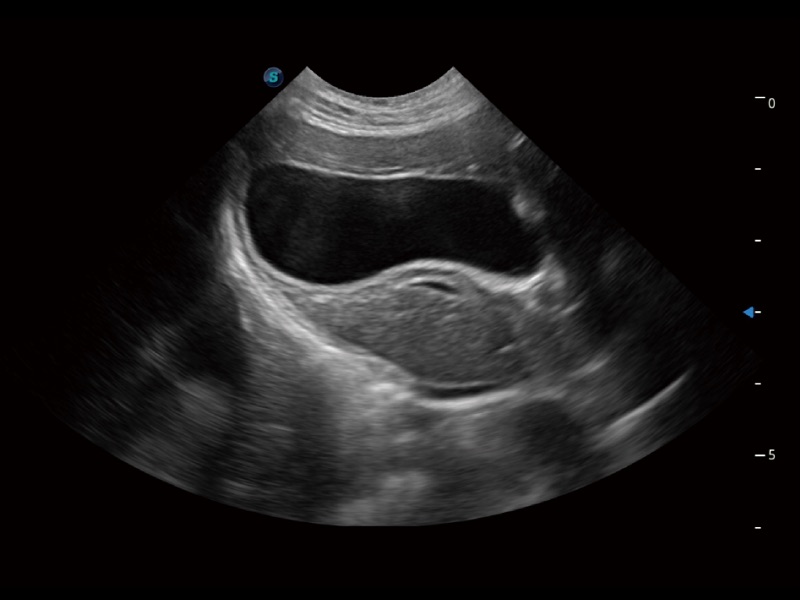

(犬)肾脏显微血流

(猫)胆囊

(猫)肺动脉血流频谱

(犬)左室长轴血流

(犬)髂动脉血流

(犬)四腔心

(犬)胎儿主动脉弓立体血流

(犬)肝脏

(犬)四腔心MQA